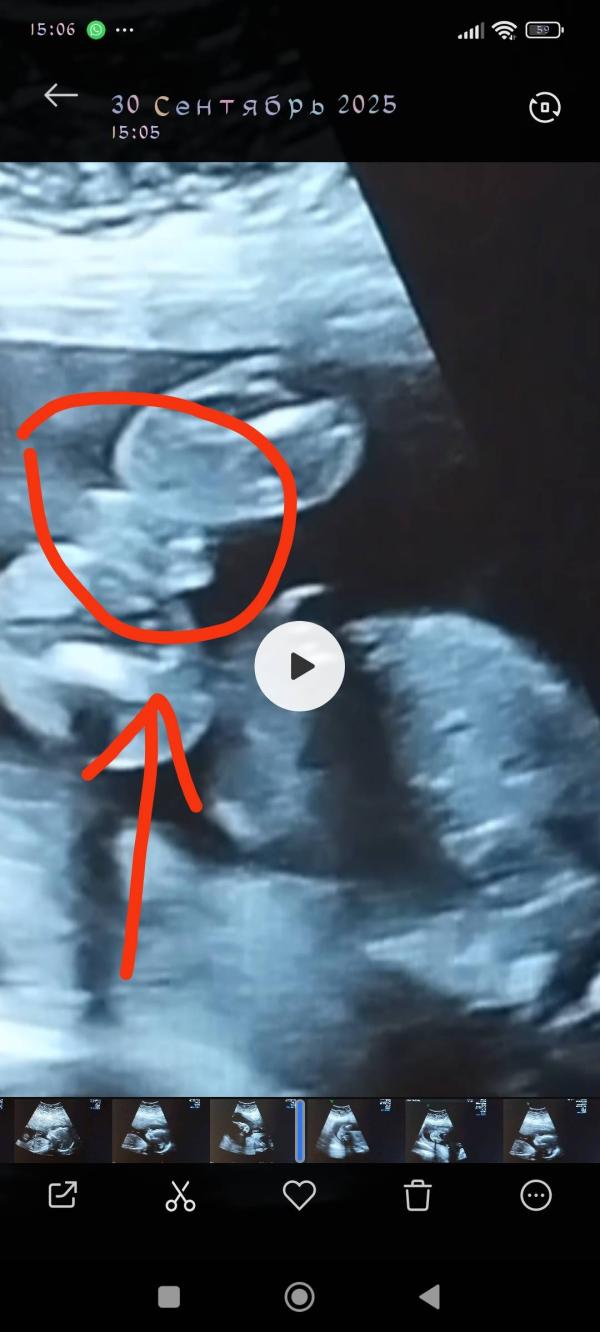

Прошли второй скрининг, как вы думаете кто это? На фото вот в кружочке между ножек. Узистка точного ответа так и не дала😟я так поняла это мальчик вроде.

А узистка показала вот так между ножек и предположила мальчика.

@slava.kira.1962 там между ног четко кофейное зернышко)) это девочка

Если присмотреться то видно писюльку мальчика, скорее всего мальчик